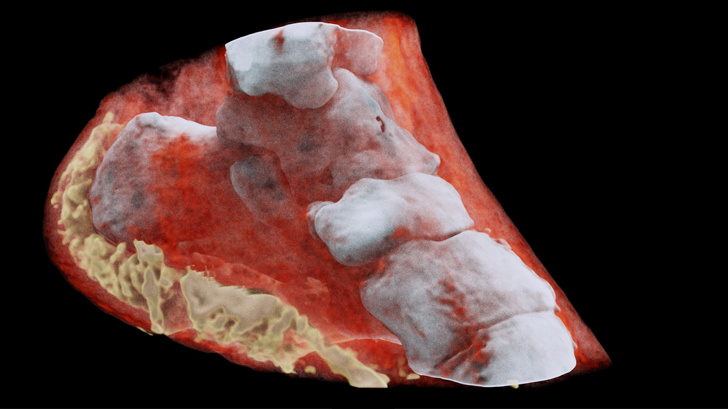

#2. The aorta is the biggest artery in our body.